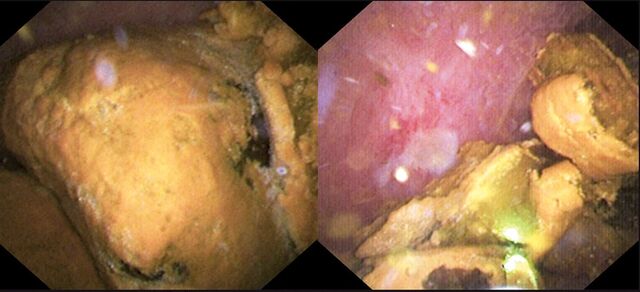

담관에 생긴 거대 결석(왼쪽)과 레이저로 부서진 결석.순천향대부천병원